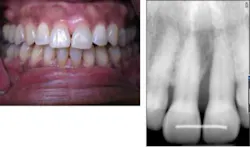

A 67-year-old African American female presented in 2001. Her diagnosis was chronic periodontitis and diabetes. Fear and anxiety resulted in refusal of osseous surgical care for bone regeneration and pocket reduction. Scaling was performed and the patient did not return for five years. She then presented with an abscess on No. 9 with significant bone loss that was not evident five years ago. Tooth No. 9 tested vital. The patient accepted the LANAP protocol. Treatment was done in January 2012.

Mrs. High Anxiety before the LANAP protocol.